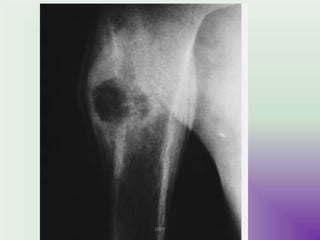

IMAGING

• X-rays

• epiphyseal

• well defined lytic lesions; either smooth or lobulated

margins with a thin sclerotic rim

• Internal calcifications can be seen in up to 40-60% of cases

• They range in size from 1-10cm, with most being 3-4cm at

diagnosis

• CT

• better delineation of the relationship to the growth plate

and articular surface

• Solid periosteal reaction (seen in up to 50% of cases) and

internal calcification (calcified matrix seen in ~ 1/2 of cases)

and cortical breach are also more easily appreciated.

• Endosteal scalloping may be seenUMY

image